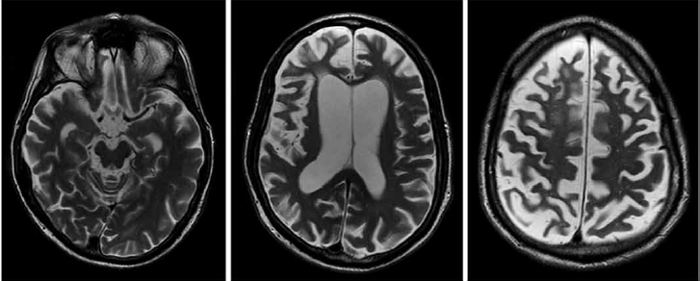

Observe a ressonância magnética a seguir.

Um homem de 65 anos apresenta-se para avaliação neurológica com queixas de movimentos involuntários lentos e contorcidos afetando principalmente os membros superiores. Ele relata que esses sintomas começaram há cerca de dois anos e têm piorado progressivamente, interferindo nas atividades diárias, como escrever e manusear utensílios. O exame físico revela distonia axial leve e ausência de sinais parkinsonianos. Não há histórico familiar conhecido da condição. Com base na apresentação clínica e na imagem da ressonância desse paciente, qual dos seguintes diagnósticos é mais provável?